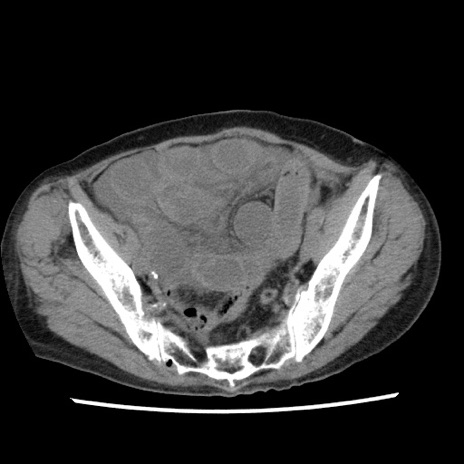

【症例】80歳代女性

【主訴】腹痛

【現病歴】8時間前から腹痛あり来院。

【既往歴】糖尿病、脂質異常症、子宮体癌にて子宮全摘術

【身体所見】意識清明・会話良好だが腹痛で苦悶様、全腹部にわたって反跳痛と圧痛あり

【データ】WBC 13600、CRP 0.14、LDH 224、CK 90